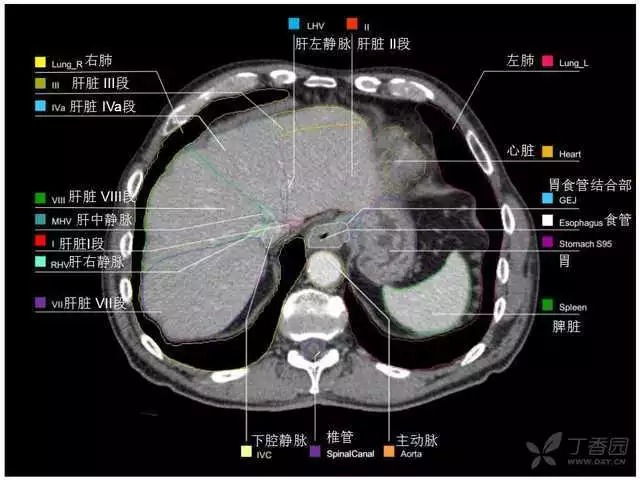

腹部肝脏高清CT断层的图谱

全腹部高清CT图谱,淋巴结彩色图谱,血管解剖图谱大汇总!

超声肝脏分叶及分段

肝脏分段和基本解剖学标志